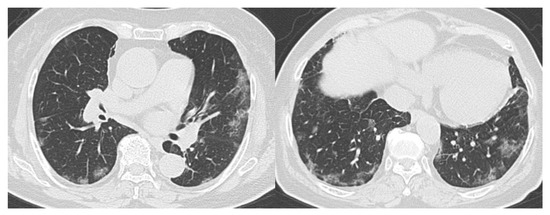

- CO-RADS 2 means a low level of suspicion for pulmonary lesion resulting from COVID-19, based on CT findings in the lungs typical of etiology indicative of infections other than COVID-19, including bronchitis, infectious bronchiolitis, bronchopneumonia, lobar pneumonia, and pulmonary abscess. Findings include a tree-in-bud sign, a centrilobular nodular pattern, lobar or segmental consolidation, and lung cavitation.